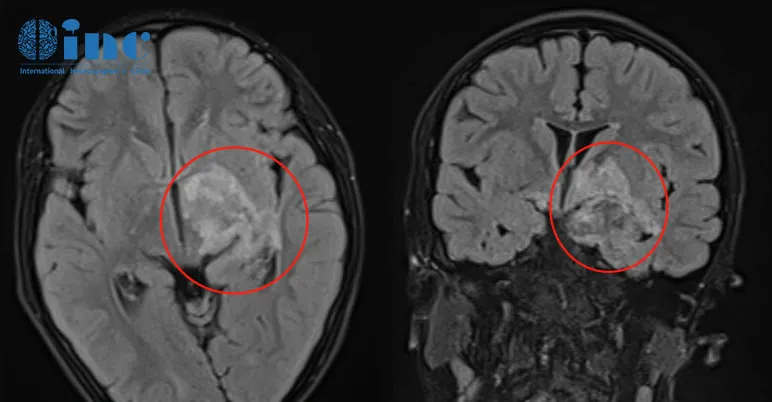

第一次术后MRI

可可和残余的肿瘤和平共处了2年,然而复查MRI发现左侧颞叶附近有一小结节增大,术前6mm,现11.1mm,已明确不是复发,是手术未注意的残留,但在增大。

MRI显示肿瘤已延伸并浸润基底节和丘脑